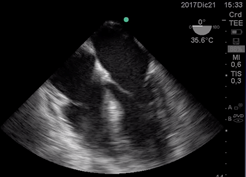

ETE en cirugía No cardíaca y PC: ETE es un monitor indicado en toda cirugía no cardíaca ante PC para un rápido reconocimiento de la causa y del estado cardiopulmonar. Además de determinar el ritmo cardíaco y la efectividad de la reanimación nos guía hacia causas reversibles de PC.

En la siguientes imágenes obsevamos algunos ejemplos de causas analizadas durante la reanimación cardiopulmonar:

En las Figuras k se obervan dos pacientes donde se obtuvieron imagenes de 4 cámaras

medioesofágica inmediatamente posterior a reanimación de PC y con fracción de eyección 15% . Uno con distención de aurícula izquierda por Sindrome de Takotsubo el otro de aurícula derecha por McConnell. (Figura k1) y (Figura k 2)